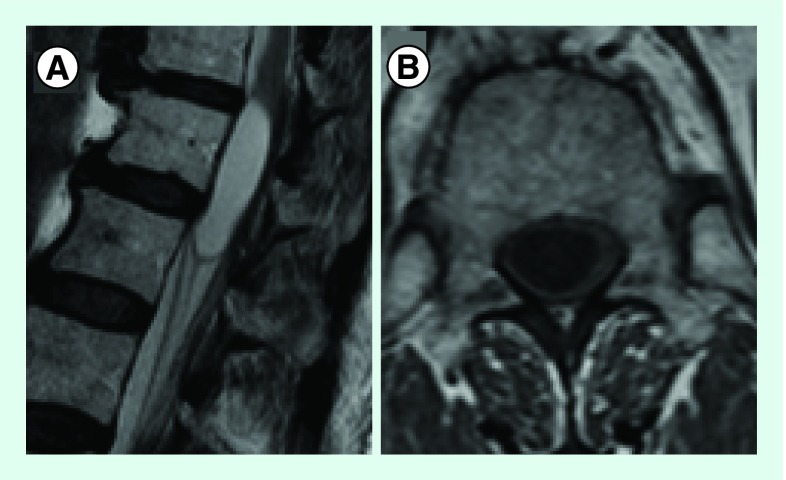

胸腰椎MRI显示一个以脊髓圆锥为中心的囊性病变(图1)。根据患者的拒绝情况,没有进行对比。麦考密克二级肿瘤入院。